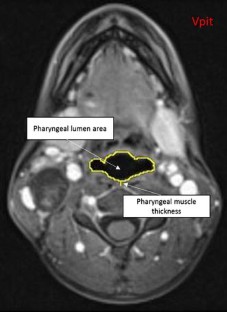

Age-related loss of muscle bulk and strength (sarcopenia) is often cited as a potential mechanism underlying age-related changes in swallowing. Our goal was to explore this phenomenon in the pharynx, specifically, by measuring pharyngeal wall thickness and pharyngeal lumen area in a sample of young versus older women. MRI scans of the neck were retrospectively reviewed from 60 women equally stratified into three age groups (20s, 60s, 70+). Four de-identified slices were extracted per scan for randomized, blinded analysis: one mid-sagittal and three axial slices were selected at the anterior inferior border of C2 and C3, and at the pit of the vallecula. Pixel-based measures of pharyngeal wall thickness and pharyngeal lumen area were completed using ImageJ and then converted to metric units. Measures of pharyngeal wall thickness and pharyngeal lumen area were compared between age groups with one-way ANOVAs using Sidak adjustments for post-hoc pairwise comparisons. A significant main effect for age was observed across all variables whereby pharyngeal wall thickness decreased and pharyngeal lumen area increased with advancing age. Pairwise comparisons revealed significant differences between 20s versus 70+ for all variables and 20s versus 60s for all variables except those measured at C2. Effect sizes ranged from 0.54 to 1.34. Consistent with existing sacropenia literature, the pharyngeal muscles appear to atrophy with age and consequently, the size of the pharyngeal lumen increases.

Fig. 1